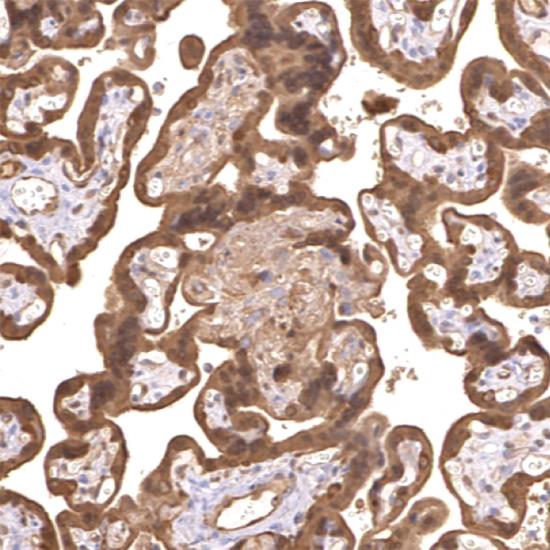

鼠抗人基質(zhì)金屬蛋白酶-2(MMP-2)單克隆抗體

• 陽(yáng)性部位:

細(xì)胞漿

• 陽(yáng)性對(duì)照:

胎盤

基質(zhì)金屬蛋白酶(matrix mstalloproteinases, MMPs) 是一組依賴鋅離子而降解各種細(xì)胞外基質(zhì)的蛋白酶,亦稱IV膠原酶或稱明膠酶A,其主要功能為降解IV型膠原,因而它在腫瘤細(xì)胞突破基底膜屏障和浸潤(rùn)轉(zhuǎn)移中起重要作用。MMP-2是分子量為72kDa的明膠酶A,主要由巨噬細(xì)胞、結(jié)締組織細(xì)胞和某些腫瘤細(xì)胞合成分秘,它可以降解IV、V、IX、XI型膠原,與某些生理功能(如組織發(fā)生、傷口愈合等)和病理過(guò)程(如腫瘤的浸潤(rùn)和轉(zhuǎn)移)密切相關(guān)。此抗體主要用于各種惡性腫瘤的研究。